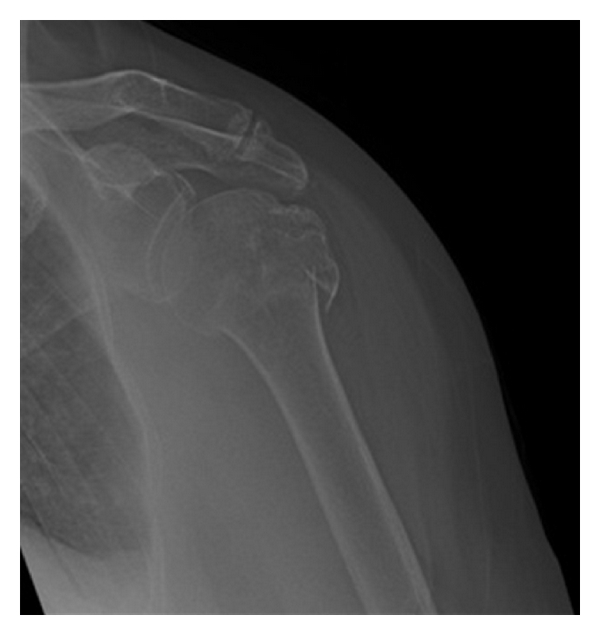

A 76-year-old independent lady sustained a low energy mechanical fall. She presented to the emergency department with a closed, neurovascularly intact isolated injury to her left shoulder. Radiographs confirm a minimally displaced 3-part fracture of her left proximal humerus (Figure 1).

(a)

(b)